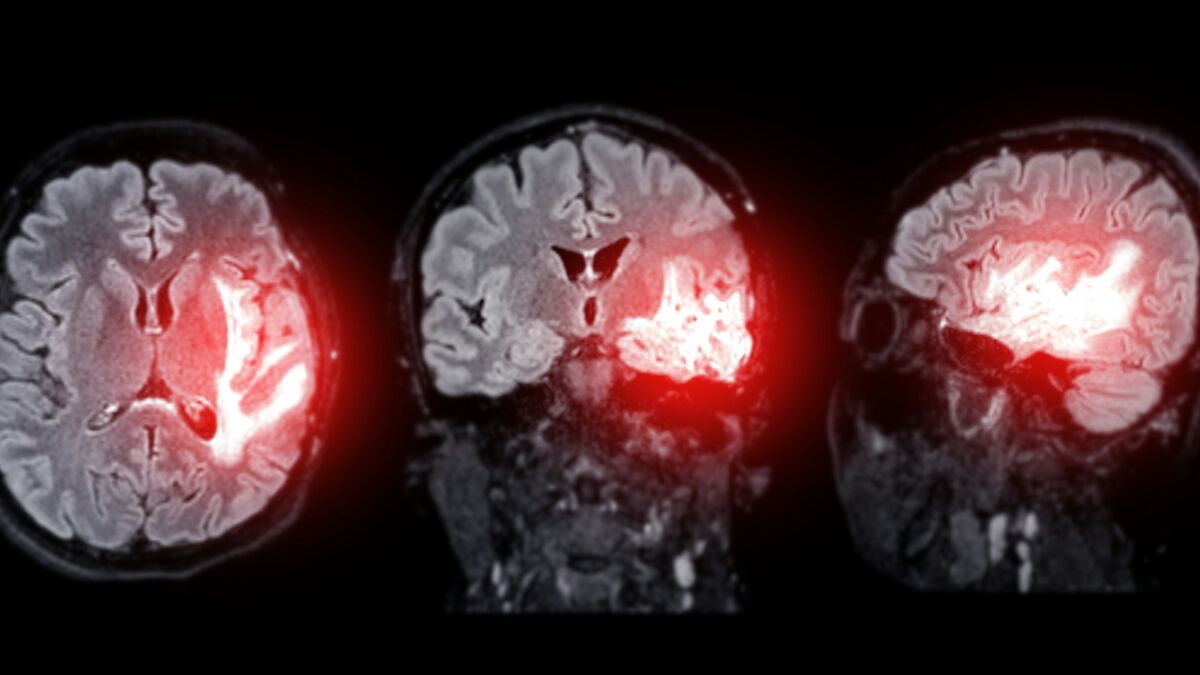

“In rare cases the sudden spike in pressure can rupture blood vessels in the brain leading to subarachnoid hemorrhage,” which is a life-threatening condition where blood seeps between the brain and its protective membranes.

Image credits: Unsplash / Tomasz Gawłowski

He goes on to say that this risk is higher in individuals prone to aneurysms and weakened arteries.